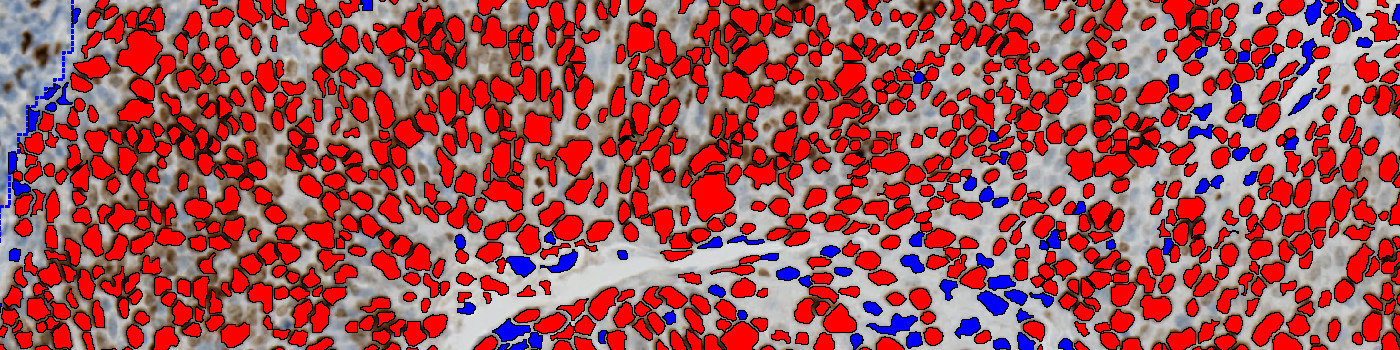

Tumor areas are automatically detected from the CK5 slide and outlined as regions of interest (ROIs). The ROIs are superimposed onto the aligned Ki-67 tissue slide to outline the tumor region on the Ki-67 slide. The subsequent analysis is now limited to the inside of the tumor regions only.

Ki-67 negative and positive nuclei are detected and delineated from their surroundings to accurately quantify nuclei in highly concentrated areas.